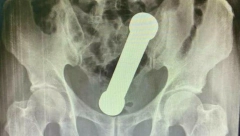

TEG OD 2 KG U REKTUMU Žalio se na bolove u stomaku, a kada su lekari videli rendgenski snimak nisu mogli da veruju!